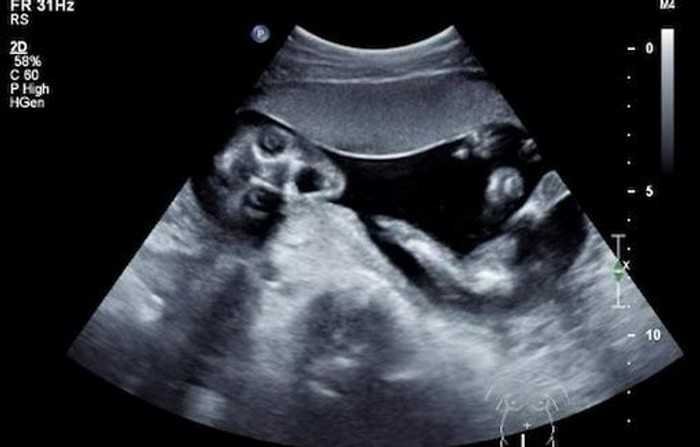

2 – Quando você faz o ultrassom do seu filho e ele aparece assim: